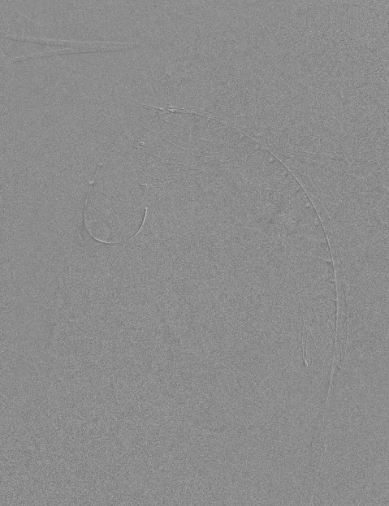

3、造影确认后,快速释放主体支架,助手配合牵拉分支导丝释放分支支架;

动脉长鞘怎么置入【弓部重建直通车】真腔难觅,另辟蹊径|潍坊市人民医院血管外科运用Castor®支架结合长鞘建立导丝通路治疗主动脉夹层两例_https://www.jmylbn.com_新闻资讯_第17张

释放支架